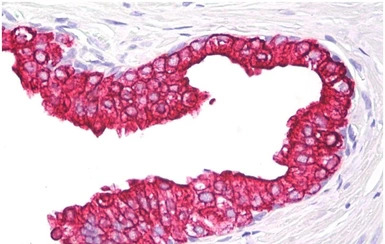

IHC-P analysis of human prostate tissue using GTX22535 Cytokeratin 5 + 18 antibody [C-50].